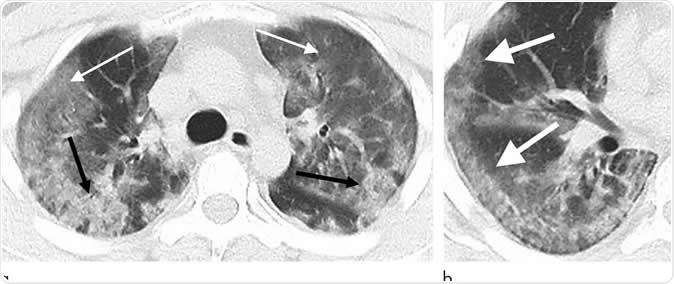

29-year old male with unknown exposure history, presenting with fever and cough, ultimately requiring intensive care unit admission. (a) Axial thin-section non-contrast CT scan shows diffuse bilateral confluent and patchy ground-glass (solid arrows) and consolidative (dashed arrows) pulmonary opacities. (b) The disease in the right middle and lower lobes has a striking peripheral distribution (arrow). Image Credit: Radiological Society of North America

CT scan images of these patients’ chests revealed certain common features including, ground glass opacities and consolidation features over the lungs. The team also noted the number of lobes of the lungs that were affected with ground glass opacities and consolidation and the degree of involvement of each of these lobes of the lungs. Based on these the team also looked at the overall total severity scores. They also noted absence of nodules in the lungs and fluid in the pleural cavity (pleural effusion). There was involvement of some of the lymph nodes of the thorax and these were abnormal in size and shape, they wrote. Some of the patients also had underlying lung diseases such as fibrosis and emphysema. These features were all recorded for the patients with the coronavirus infections. The team found some additional features such as crazy paving patterns and distribution of the changes in the peripheral parts of the lungs. There may be absence of cavity formation within the lungs along with some clear-cut nodules, they wrote. Pleural effusions and lymphadenopathy may also be absent they wrote.

Among seven of the eight patients, there was a slow progression of the lung disease with rising areas of airspace opacities, they wrote. The team wrote in their study, “Typical CT findings included bilateral pulmonary parenchymal ground-glass and consolidative pulmonary opacities, sometimes with a rounded morphology and a peripheral lung distribution.”